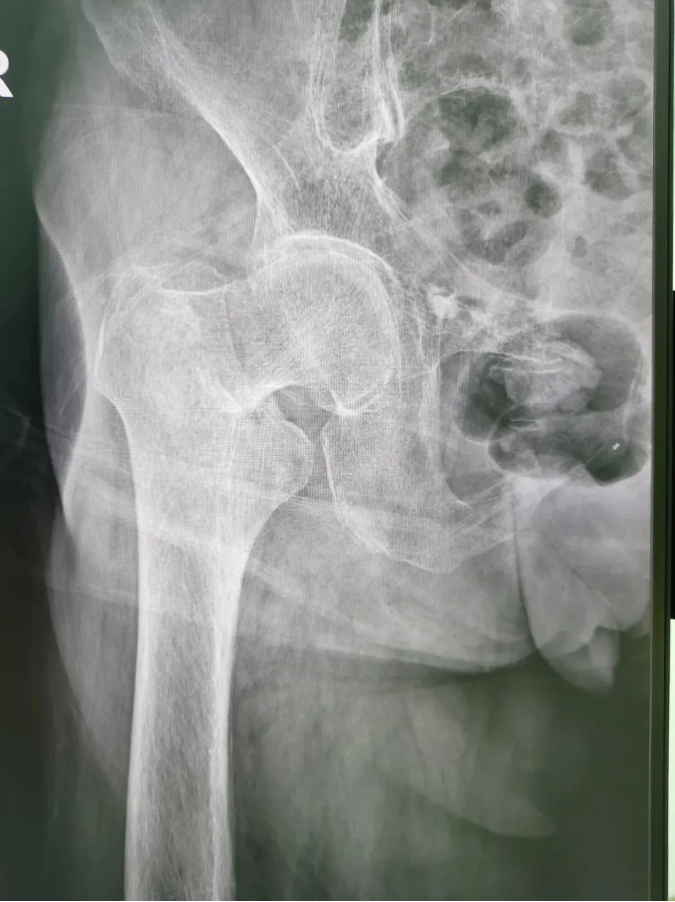

今年91歲的陳婆婆,9月份時在家不慎摔倒,右臀部著地,當下感到髖部劇烈疼痛并活動受限。為求進一步治療,到順德和平外科醫(yī)院骨三區(qū)就診,該區(qū)主任楊升平主任為其診療,被診斷為“右股骨頸骨折”,需進行右股骨頸骨折經(jīng)皮閉合復位空心螺釘內(nèi)固定手術。

術前X光

陳婆婆91歲的高齡,有高血壓和冠心病病史,通過傳統(tǒng)開刀手術治療風險較大。經(jīng)骨三區(qū)專業(yè)醫(yī)療團隊討論,決定讓天璣?骨科機器人上場,輔助完成微創(chuàng)手術。